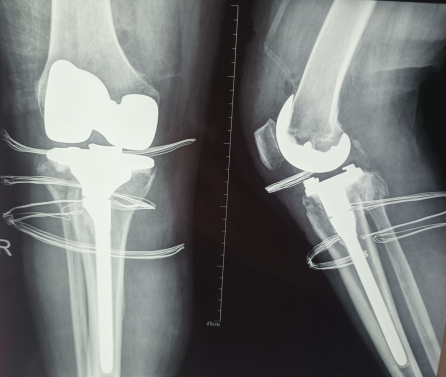

“采用膝關(guān)節(jié)置換術(shù)、脛骨假體術(shù)中加入延長(zhǎng)桿,不僅能治療粉碎性骨折、加強(qiáng)人工關(guān)節(jié)的穩(wěn)定性,同時(shí)也消除了骨性關(guān)節(jié)炎造成的疼痛隱患,術(shù)后也不會(huì)繼發(fā)疼痛、關(guān)節(jié)炎等。一次治療,可以解決兩個(gè)問(wèn)題”,王教授說(shuō)。

在王教授強(qiáng)有力的技術(shù)支撐和手術(shù)室、外二科團(tuán)隊(duì)的默契配合下,黃奶奶的手術(shù)非常成功,術(shù)后轉(zhuǎn)入外二科病房,接受進(jìn)一步治療。目前,一切良好、正在恢復(fù)。

據(jù)主管醫(yī)生了解,黃奶奶麻醉醒了之后,膝關(guān)節(jié)就能活動(dòng)了,術(shù)后復(fù)查X光片假體位置良好。更是掩飾不住欣喜,為王教授點(diǎn)贊,向醫(yī)護(hù)團(tuán)隊(duì)說(shuō),“謝謝……”

(術(shù)后復(fù)查X光片假體位置良好,力線正常)